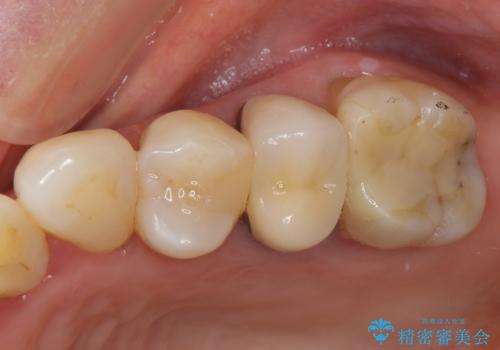

オールセラミッククラウン 欠けてしまった奥歯の治療